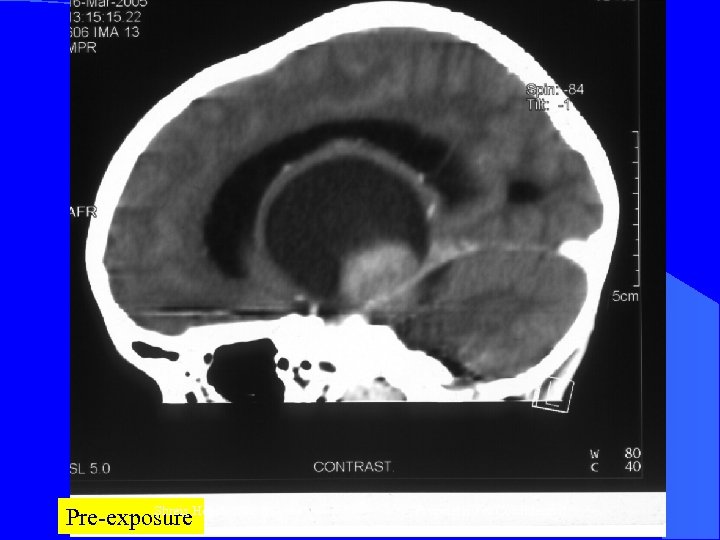

CASE 3 Mr RG, 5 yrs l May 2004 – Right Hemiparesis with ICSOL - MRI – Left Thalamic glioma with systi changes obst. Hydrocephalus - Op n = Right VP shunt - Neuro improvement l Jun 2004 – Neuro deterioration - Op n = Revision of VP shunt l. l Shreis Health Inc. Proprietary & Confidential

At Presentation – Nov 04 - ® Hemiparesis -Headache -Diplopia RFQMR – Nov 2004 Today - No increase ICT - Mild residual ® Hemiparesis Shreis Health Inc. Proprietary & Confidential

Shreis Health Inc. Pre-exposure Proprietary & Confidential